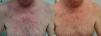

El tratamiento de la erupción se inició cuanto antes para controlar la toxicidad cutánea y evitar interrupciones innecesarias del tratamiento antitumoral. En la figura 2 se resume el algoritmo terapéutico que seguimos en nuestro servicio, según la gravedad de la erupción papulopustulosa. Todos los pacientes con erupciones grado 2-3 fueron tratados con tetraciclinas orales (fig. 3A), con un adecuado control (fig. 3B). Hubo 3 casos de erupciones más resistentes que precisaron isotretinoína, 2 de ellos con buena respuesta. El tercero no toleró la medicación, lo que obligó a suspender el tratamiento anti-EGFR.